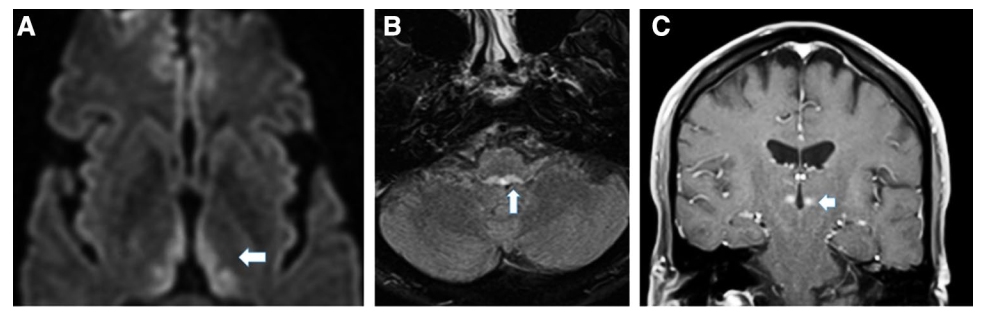

A: Aymmetric signal changes are also present in the medial thalamus (DWI);

B: Arrow points to the medial vestibular and prepostus hypoglossi nuclei (FLAIR);

C: Area of contrast enhancement in the left medial thalamus provides evidence of a disruption of the blood brain barrier during the acute phase of Wernicke's encephalopathy.